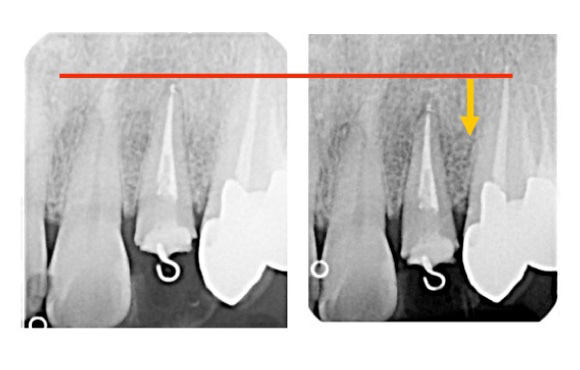

倒れている歯を起こす(アップライト)

手前の歯がなくなった後放置したことにより

奥の歯が手前に倒れこんできてこのままではブリッジやインプラント治療ができない。

バネの弾力により歯を起こしこの後インプラントやブリッジにより噛み合わせを回復することが可能になります。

手前の歯を喪失したあと、長い間放置したため手前に歯牙が傾いてしまっています。

歯牙を4か月から6か月かけて起こすことができました。